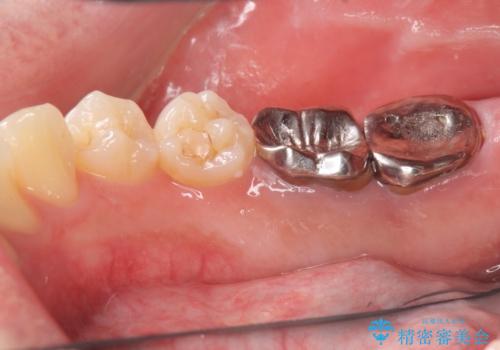

[メタルフリー] 虫歯・銀歯だらけの口腔内を全顎治療

- 銀歯だらけの見た目と、歯の磨きにくさの改善を求めて来院されました。

銀歯の下には虫歯の再発が見られたり、根尖病変や歯周病、噛み合わせといった複合的な問題が認められます。

気になっていた見た目の問題も解決され、歯の磨きやすさ、噛み合わせの安定による食事のしやすさを治療の終了後に実感していただくことができました。